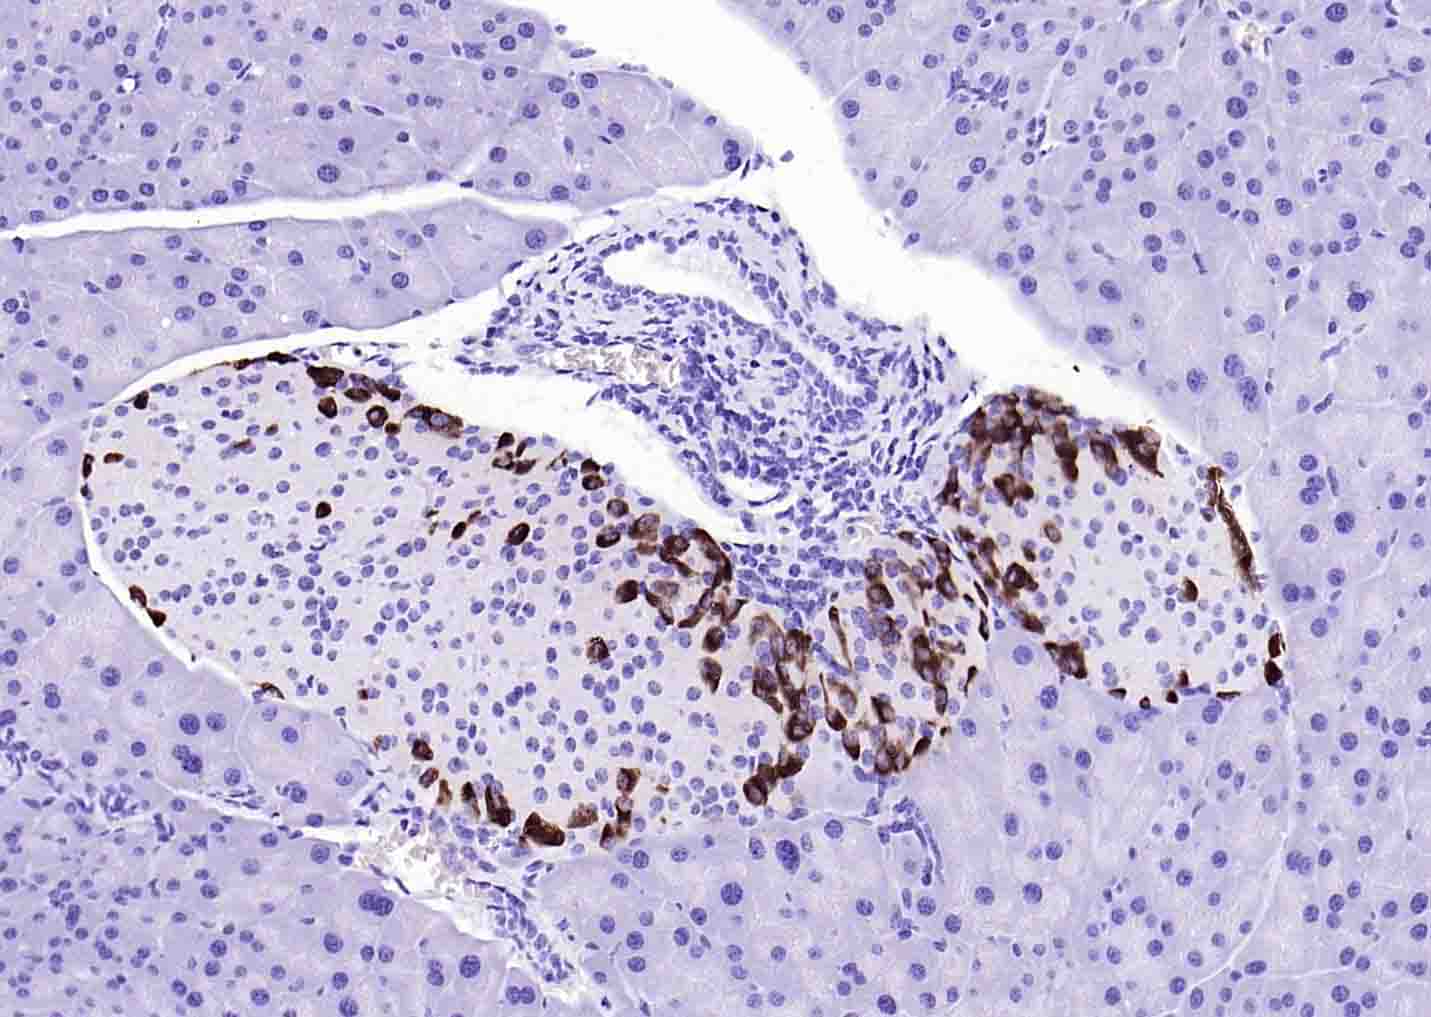

| 产品应用 | IHC-P=1:100-500, IHC-F=1:100-500, IF=1:100-500 Not yet tested in other applications. |

| {IHC-P} | {1:100-500} |

| {IHC-F} | {1:100-500} |

| {IF} | {1:100-500} |

[IF={{ 3.23 }}] {Sun, Qianqian, et al. "Factors that Affect Pancreatic Islet Cell Autophagy in Adult Rats: Evaluation of a Calorie-Restricted Diet and a High-Fat Diet."PLoS ONE 11.3 (2016): e0151104.} {IHC} {="Rat"}

We demonstrate below a double immunostaining using a pair of rabbit antibodies to glucagon (amplified at a dilution of 1:5000 on path 12) and neurofilament M (conventionally stained at a dilution of 1:2000 on path 1) in a section of non-perfused rat pancreas